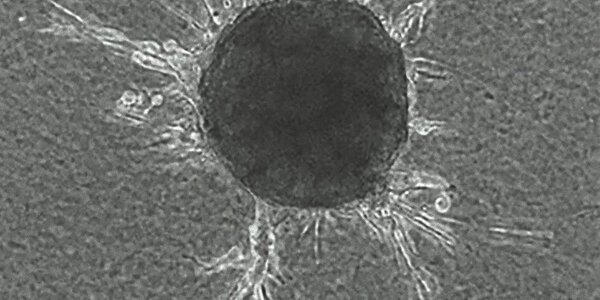

Article teaser image